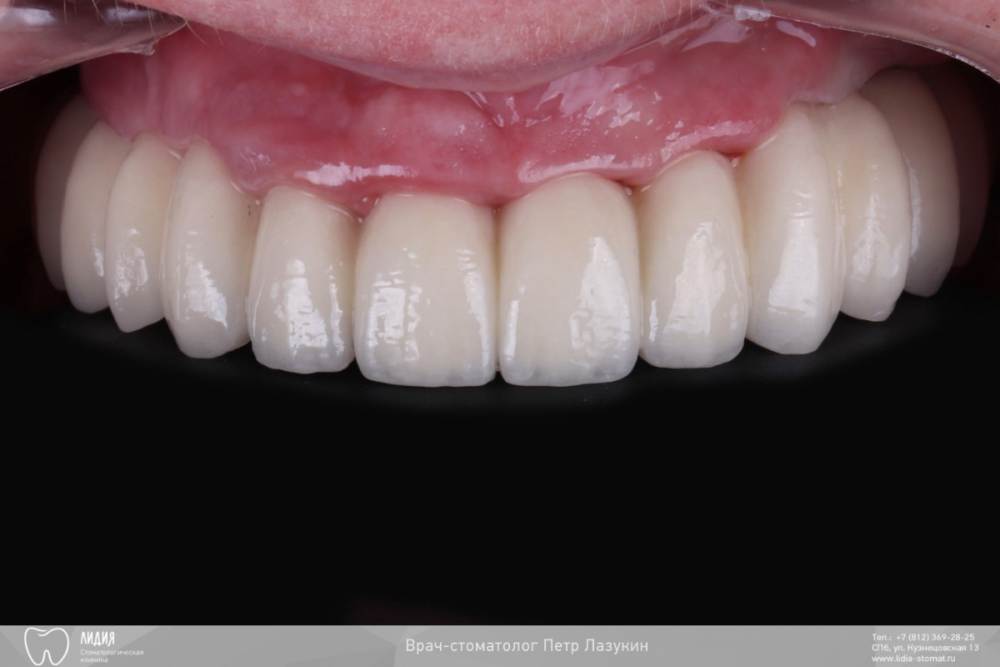

pit Опубликовано 5 октября, 2021 Поделиться Опубликовано 5 октября, 2021 Клинический случай. Старт работ в 2015 году. План простой: Полная дуга, верхняя челюсть. Начали в 2015, закончили в 2021. Какой был план? Зубы в/ч все под удаление. Фронт был временно сохранен для временного протезирования. Установлены импланты с костнопластическими манипуляциями. В качестве временных коронок использованы металлокерамические коронки. Следующим этапом, после интеграции, было открытие имплантов и изготовление временных коронок. И тут пациент пропал на 2 года, а затем еще на четыре)))). Лишь поломка времянок, через 6 лет, сподвигла пациента обратиться за изготовлением постоянных коронок. Протокол и комменты в слайдах. КТ после протезирования. 11.mov 1 2 2 Ссылка на комментарий